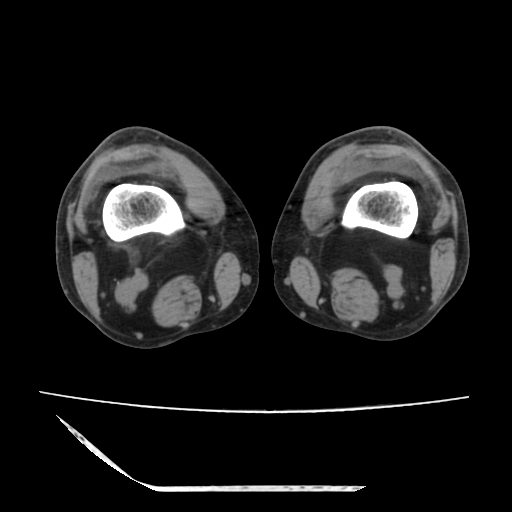

标题: CT13225:老年男性,左膝关节疼痛数月;请各位老师讨论。 [打印本页]

标题: CT13225:老年男性,左膝关节疼痛数月;请各位老师讨论。

骨质增生,骨性关节面硬化,关节积液,考虑退行性骨关节病

关节腔内少量积液,关节面退变。

双膝退变

骨质增生,骨性关节面硬化,关节间隙失常,关节积液,考虑退行性骨关节病.

骨质增生,骨性关节面硬化,关节积液,考虑退行性骨关节病。

这是由于两侧的肌肉不对称所致,加上扫描的平面也有些差异。请看示意图:

这个病例诊断:退行性骨关节炎